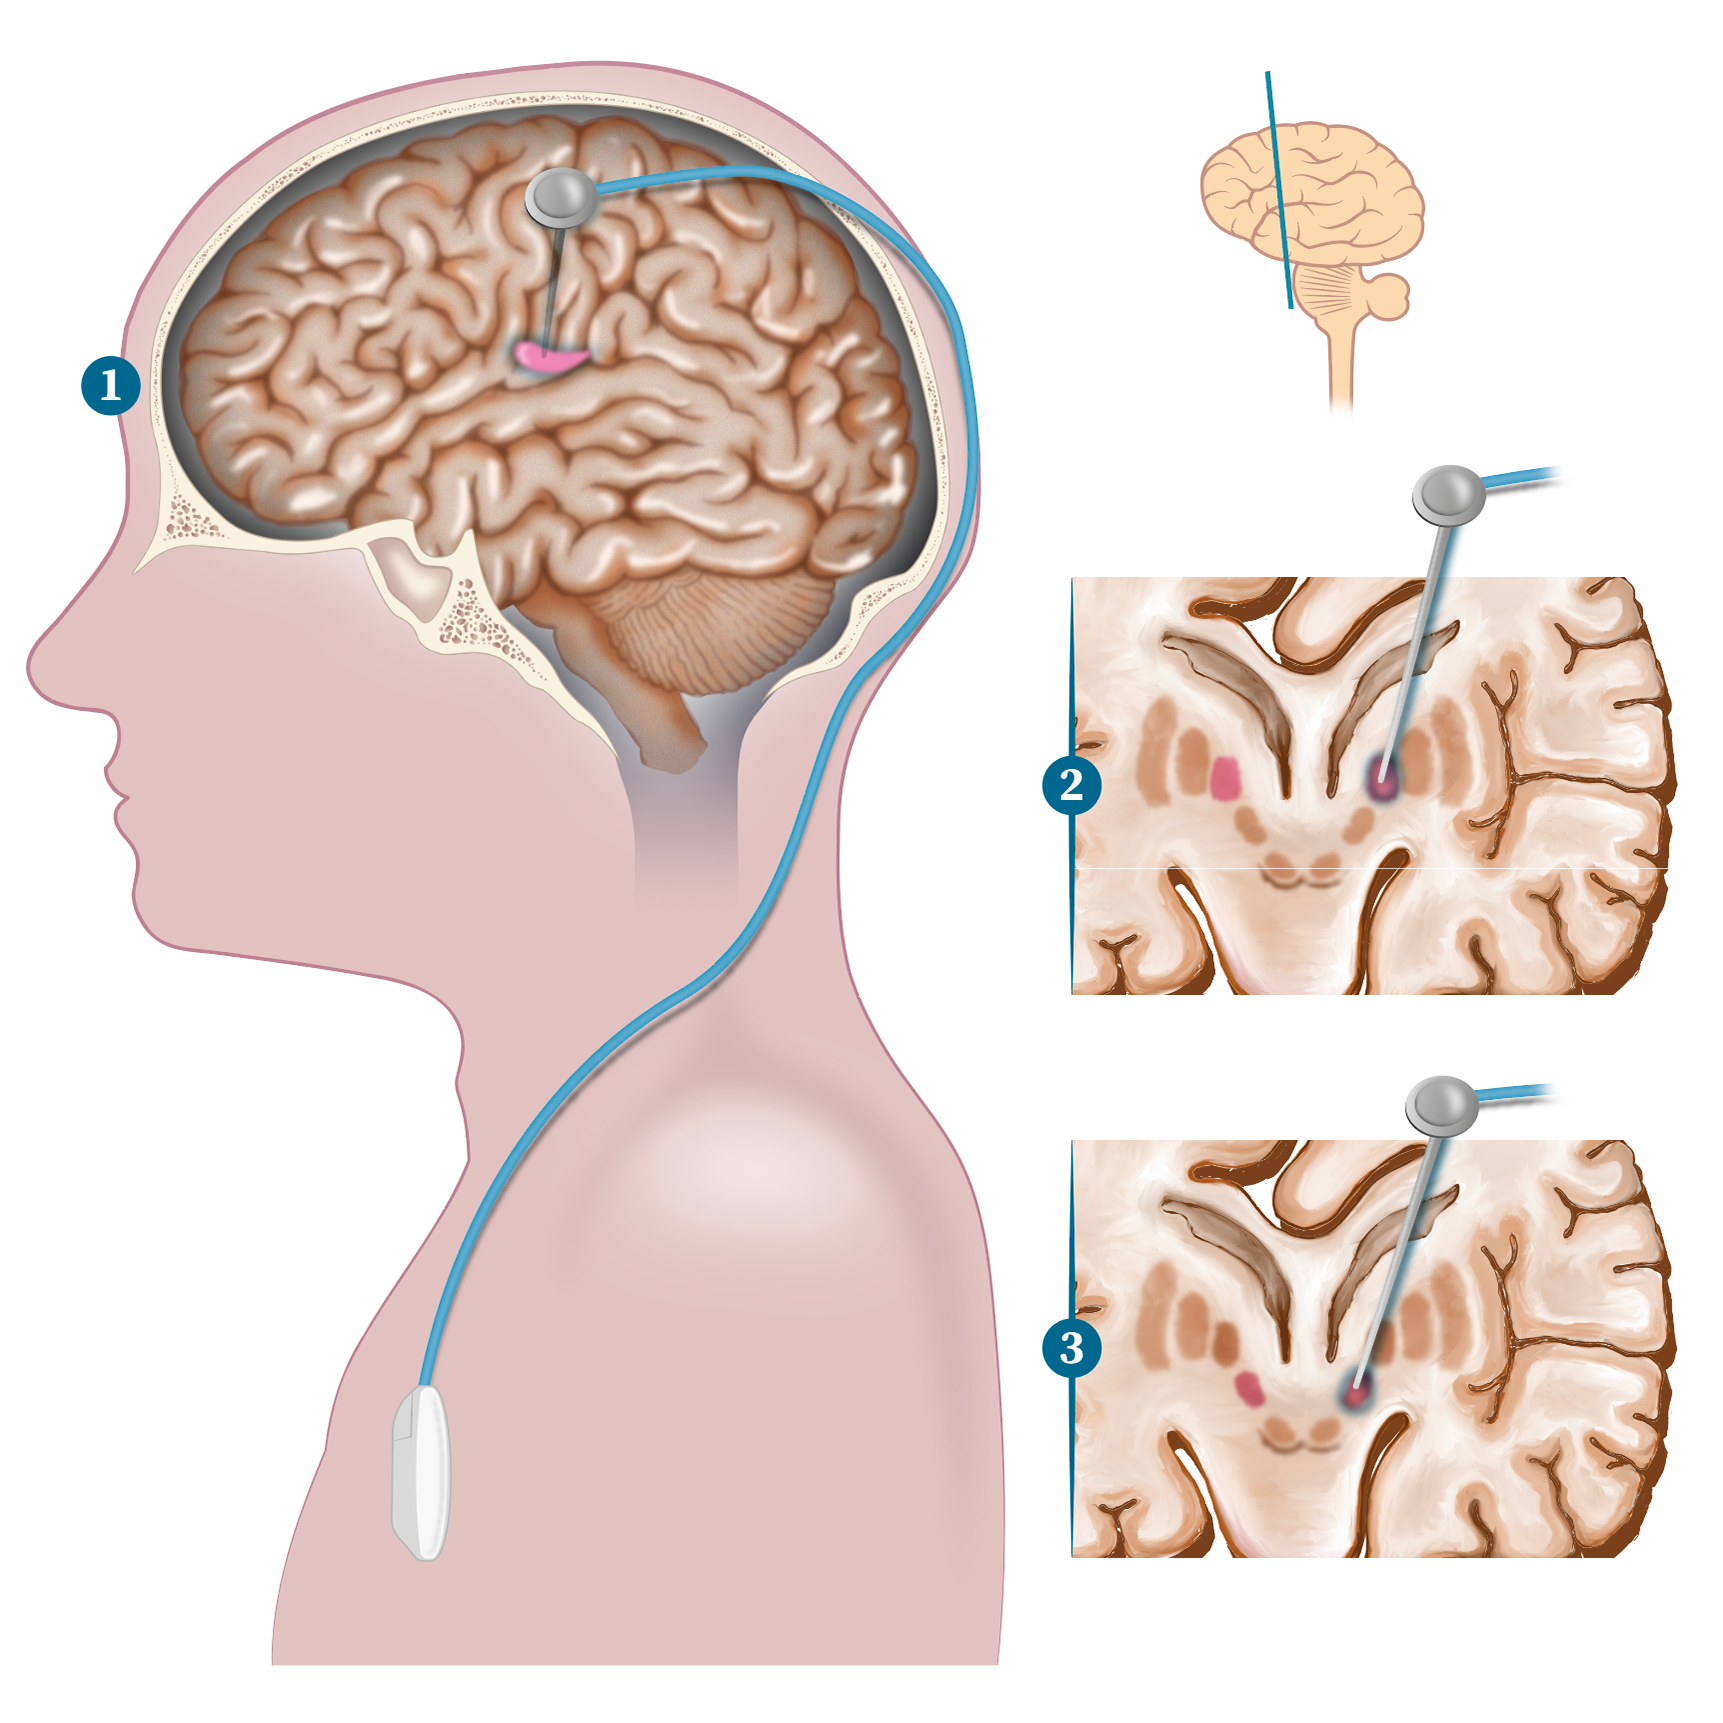

Ilustración Medica / Neurología

Neurología